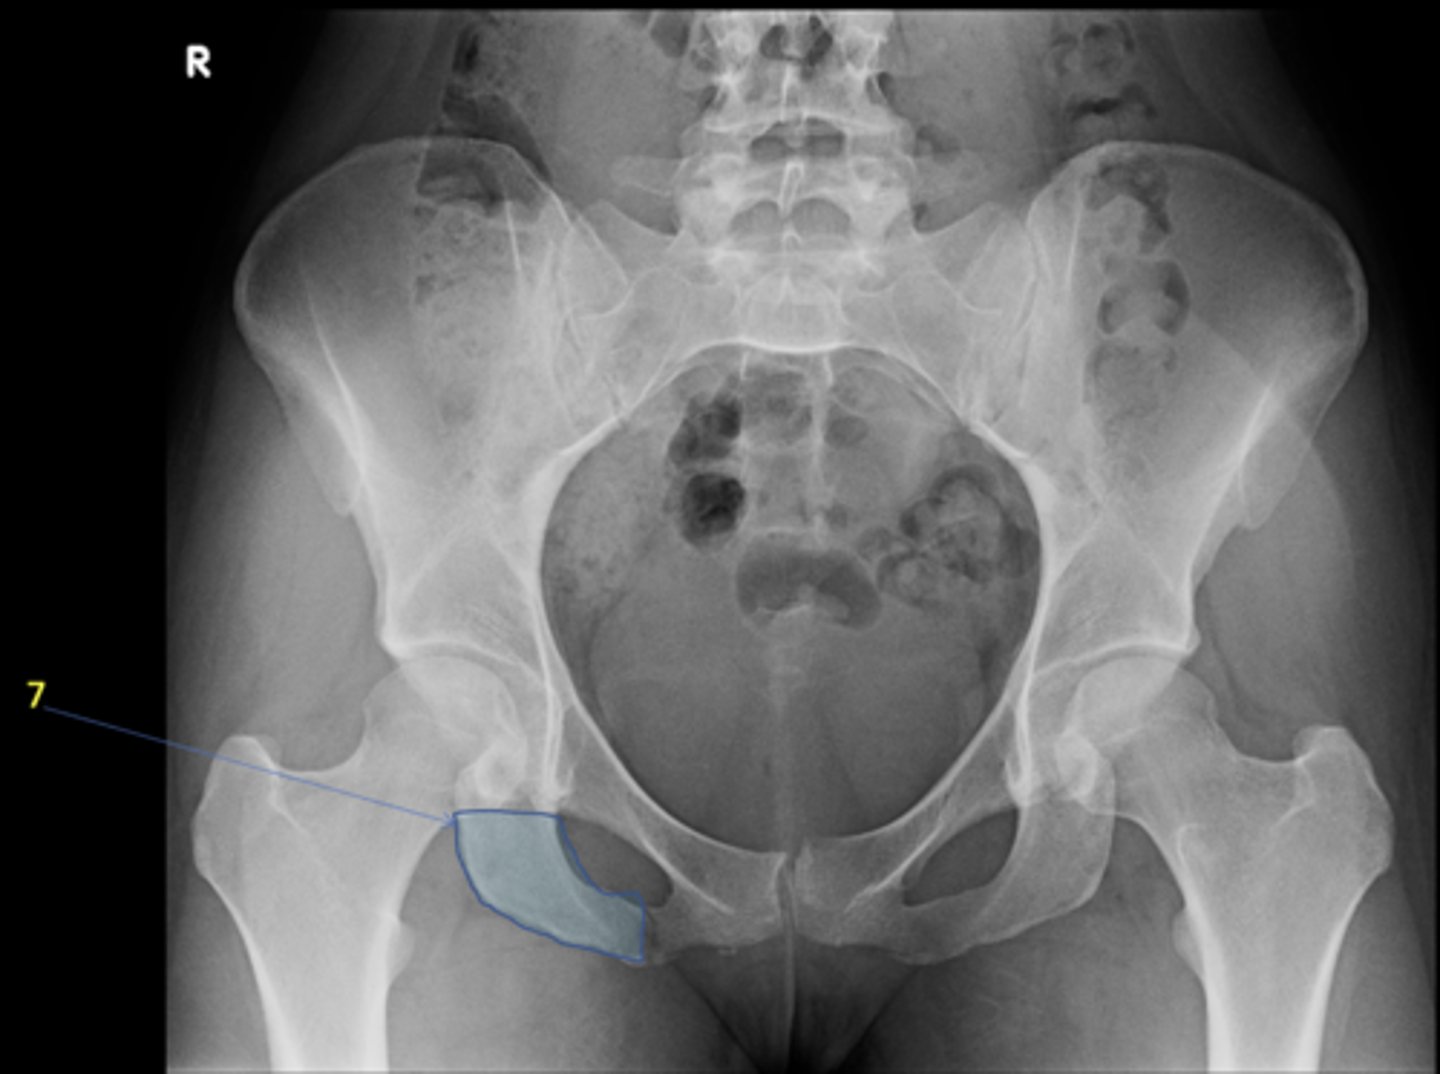

1

New cards

AP pelvis

View?

<p>View?</p>

7

Right ischium

ID 7

<p>ID 7</p>